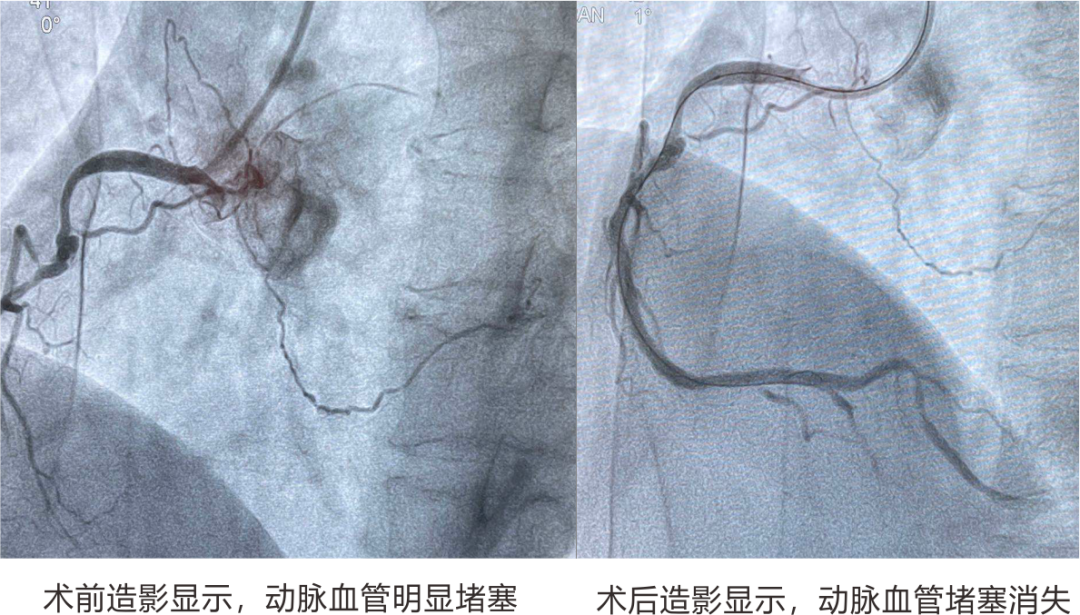

典型案例